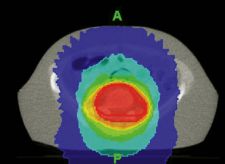

TOHCC clinicians have carefully assessed the system as a new tool for palliative care. They have observed highly conformal dose distributions that have reduced radiation dose to surrounding healthy tissues.

“We have found that dose distributions from StatRT are much more conformal than with traditional palliative techniques,” MacPherson said. “This allows for better tissue sparing and, we hope, better tolerance of treatment.”